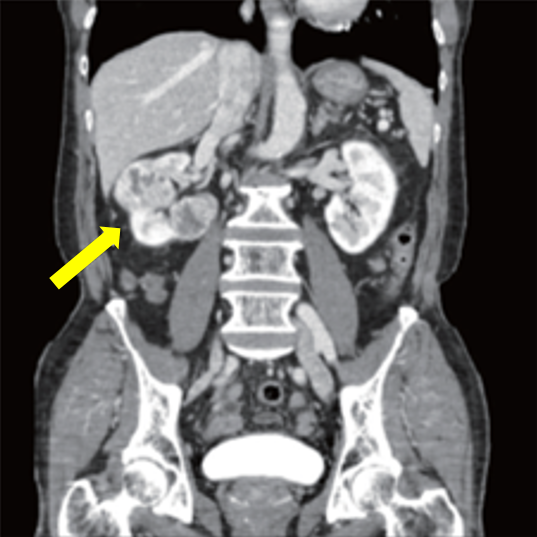

신장암은 초음파, CT, MRI 등 영상검사로 진단한다. 초음파검사로 옆구리 혹 유무를 확인하며, 혹이 확인된 경우 정확한 진단을 위해 복부CT검사를 진행한다. MRI 검사는 CT 외 추가감별진단에 도움이 되며, 특히 신세포암이 하대정맥(혈액을 심장의 우심방으로 운반하는 인체 내 가장 큰 정맥)을 침범하여 혈관 속 종양이 존재하는 경우 그 범위를 평가하는 데 사용된다.

신장암이 전이되어 간, 대장, 췌장 등 주변 장기로 침범한 경우에도 CT 검사로 진단이 가능하다. 뼈로 전이되는 경우에는 방사성동위원소를 이용한 뼈 스캔 검사를 시행한다. 신장암은 수술로 완치되어도 5년 이후 재발하는 경우가 종종 있기 때문에, CT 등 영상검사를 주기적으로 받을 필요가 있다.